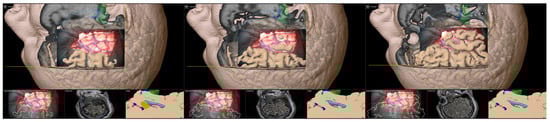

An overview of the overall workflow is provided in Figure 1, and a detailed description of all procedural steps can be found in the following.

Figure 1. Overall workflow of the presented approach to MTLE surgery investigating intraoperative computed tomography (iCT), navigated intraoperative ultrasound (iUS), and augmented reality (AR) support.